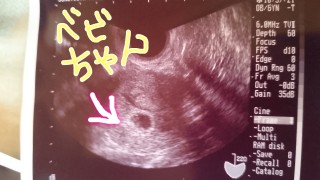

排卵日がずれていたのか生理予定日の一週間後に病院にいったけどなにも見えずさらに一週間たった今日行ったらちゃんと見えてました!初めてのベビちゃん無事に育ってくれますように。